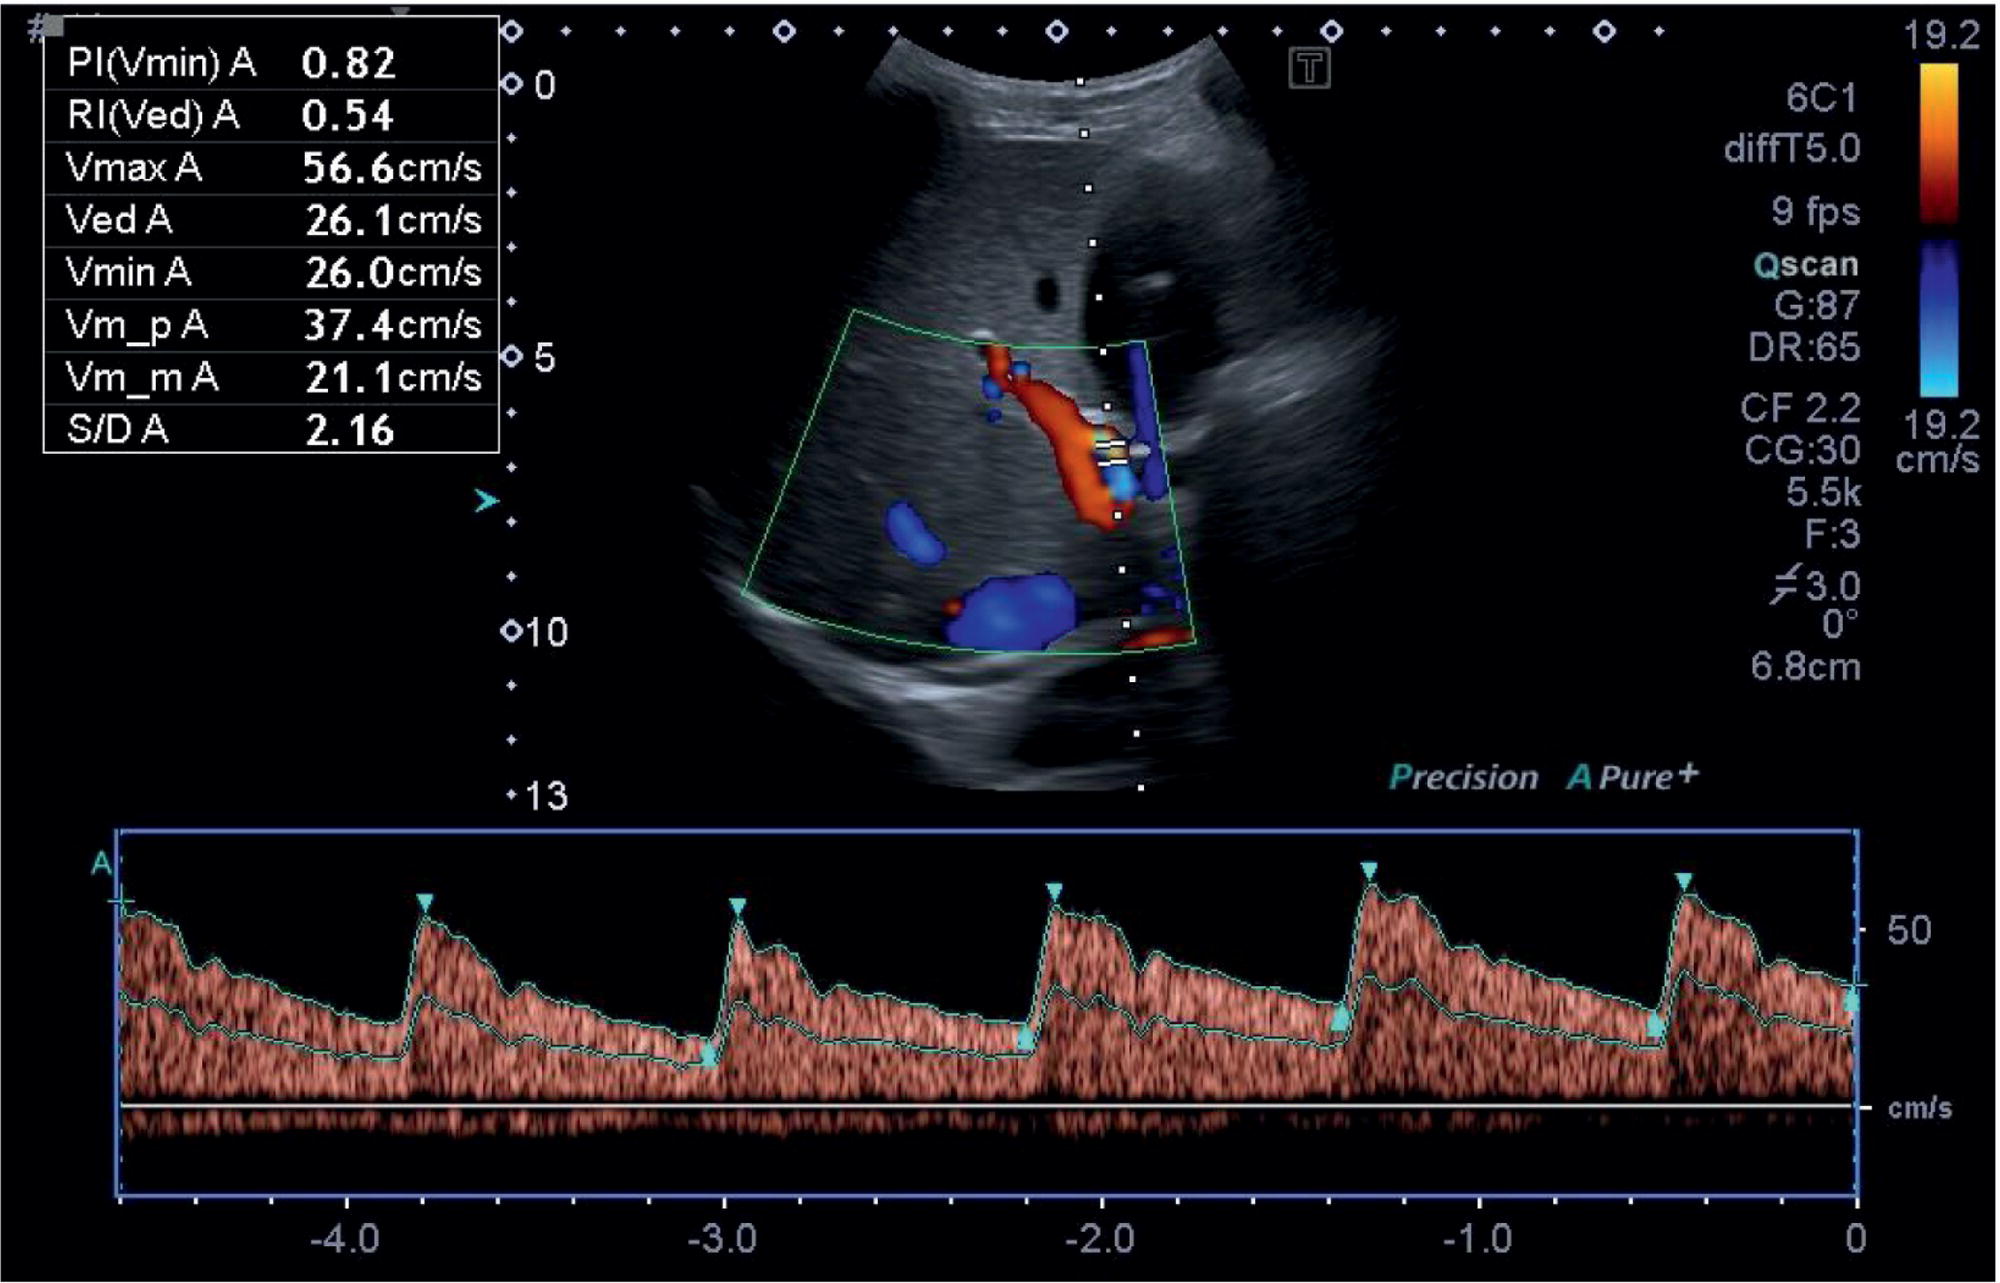

The confluence of the hepatic veins in the subcostal oblique view provides a good starting point to visualise their patency. From there the LHV, MHV, and RHV can be visualised along their entirety to the IVC with B‐mode and colour Doppler. These should also be assessed with spectral Doppler, best in the longitudinal plane, primarily to assess the flow phasicity (Figure 3.37) [9]. An assessment of the HA is usually not performed for routine clinical purposes. However, there has been much work assessing the Doppler flow of the HA in research studies for chronic liver disease [10–12]. The HA is typically visualised at the porta hepatis and in the longitudinal plane. A spectral Doppler trace allows measurement of the velocities and resistive index (Figure 3.38). Note that there are anatomical variants of the origin of the hepatic artery, which can be difficult to ascertain on occasion especially with ultrasound.